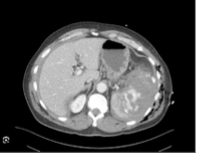

This imaging modality is the gold standard for identifying solid organ injuries in stable blunt abdominal trauma patients

What is CT scan?